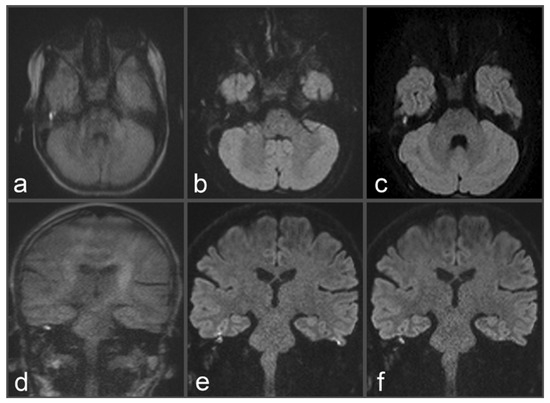

Figure 2. Images of a 48-year-old patient with a suspected cholesteatoma on the left side. (a) tseDWI. (b) uncorrected rsDWI. (c) topup-corrected rsDWI (each sample image in coronal slice orientation). Both tseDWI and topup-corrected rsDWI show a small hyperintense lesion in the upper middle ear on the left side, which could be confirmed as a cholesteatoma after surgery and histopathological examination. In contrast, uncorrected rsDWI was not able to delineate the cholesteatoma on the left side with comparable hyperintense signal intensity and shows a strong geometrical distortion of the lesion. Additionally, uncorrected rsDWI demonstrates two additional lesions: punctual on the left lateral side and brightly appearing on the right side; both were valued as artifacts due to their absence in tseDWI and topup-corrected rsDWI, respectively.